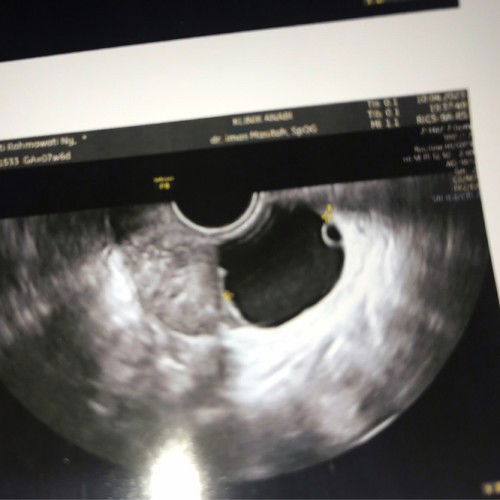

Kalau sesuai hpht usia kehamilan ku saat periksa 3 hari lalu 7 weeks 6 days. Tp saat periksa ga ada kantong kehamilan di rahim, malah ada kista di sebelah kanan ovarium. Tp kata dokternya ini jg mirip kantung kehamilan trs yg bulatan kecil di dalamnya kaya kuning telur. Ko aku jd kefikiran yah takut itu kantong kehamilan. Adakah yg pernah ngalamin bunda?#pleasehelp #pregnancy #kista #hamil7minggu